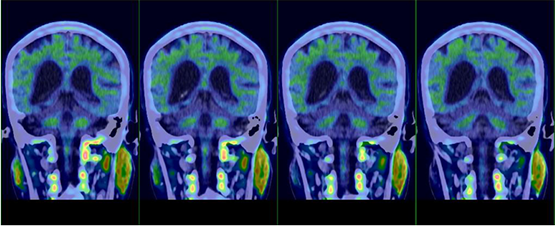

Preoperative precise diagnosis with PET-CT

The Departments of Neurology, Burn and Plastic Surgery, and Anesthesia of the Affiliated Hospital of Zunyi Medical University are all national clinical key specialties. The patient in this case was selected by Prof. YANG Xiaoyan of the Department of Neurology in person and admitted to the Department of Burn and Plastic Surgery. PET-CT, MRI and other examinations were performed preoperatively. The surgery was operated by Prof. DENG Chengliang of the Department of Burn and Plastic Surgery. He accurately exposed the lymph vessels during the surgery, performed an anastomosis under microscope, and completed the LVA surgery independently, while Prof. WANG Haiying of the Department of Anesthesia continuously checked on the patient’s condition. The surgery was greatly effective, which marks a new breakthrough of AD treatment of the hospital.